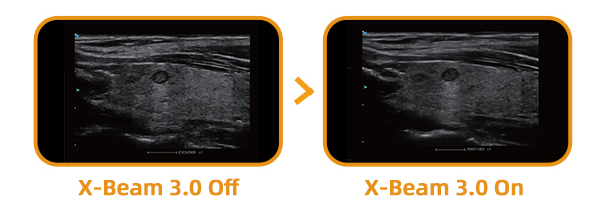

X-Beam 3.0 multiply receives and processes scanning lines of images from each element to improve image resolution and reduce tissue shadows.